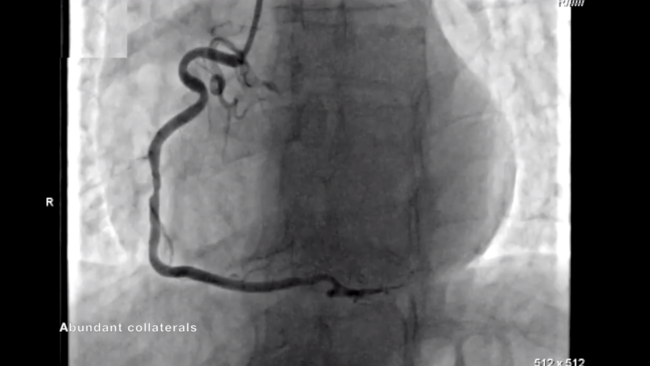

A 60-year-old male with chronic obstructive pulmonary disease and active smoking was admitted for positive treadmill test. He reported exertional chest pain 4 months ago; however, since then he had been symptom free. Echocardiography showed severe anteroseptal and mild inferoposterior hypokinesia, preserved wall thickness, and moderately reduced left ventricular ejection fraction. Coronary angiography revealed non-calcified chronic total occlusion (CTO) of the left main (LM) with microchannel toward the left circumflex (CX) artery.